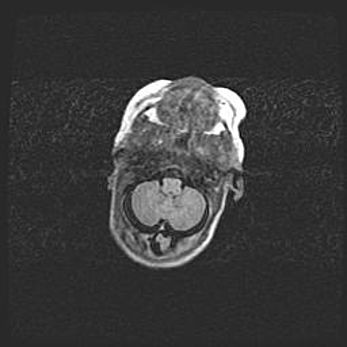

Подострая гематома правой гемисферы мозжечка.

Наружная гидроцефалия.

Возраст: 15 дней

Вес: 3100 г

Пол: женский

Окружность головы: 37 см

Срок гестации: 35-36 недель

При открытой наружной форме гидроцефалии у новорожденных расширяются и переполняются субарахноидные пространства.

Кровоизлияния в мозжечок имеют две клинико-анатомические формы: полушарные гематомы и кровоизлияния в червь.

К появлению этой патологии может привести: повреждения головного мозга, возникающие в результате асфиксии и гипоксии плода при беременности, или травмы во время родов. Редко гематома мозжечка может быть результатом первичной коагулопатии и сосудистой мальформации, диссеминированном внутрисосудистом свертывании, изоиммунной тромбоцитопении.